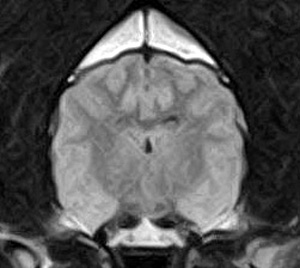

けいれん発作が出るワンちゃんが来院されました。MRI検査では脳に構造上の異常を認めず、特発性てんかんとの診断でお薬での治療となりました。発作は現在のところ、お薬で良好にコントロールされています。